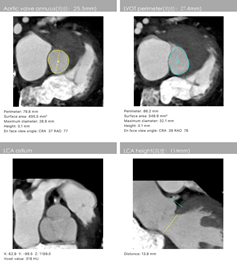

主动脉CT

陈凯明、刘浪教授团队术前总结了该病例特点:此例患者为单纯主动脉瓣返流,升主动脉直径41mm,瓣环周长79.8 mm,流出道周长86.2 mm,左心室扩大明显,特别是主动脉瓣环和瓣叶没有钙化组织, 升主动脉增宽, 喇叭口型左室流出道。这些特殊解剖特点使TAVR支架瓣膜锚定难度大,术中或术后可能出现瓣膜移位等严重并发症。这使得瓣膜的精准定位和释放极为关键。